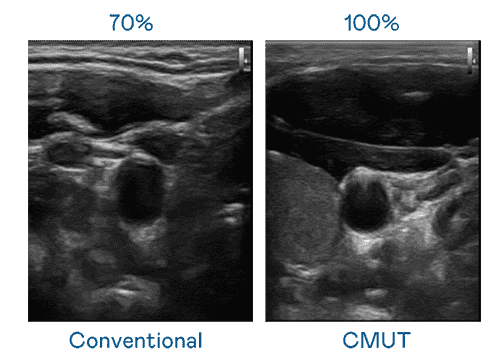

CMUT 技术是一种用电容式微机电元件来产生超音波讯号的技术。。与传统 PZT 压电式技术相比,,,CMUT 频宽增加 30%,,更宽频的超音波讯号让影像解析度大幅提升,,,,是实现高影像品质医疗超音波扫描、、促进精准医疗发展的关键技术。。

大频宽带来超清晰影像

超音波影像的解析度高低,,,首先取决于探头能发出的讯号频宽。。彩运网 CMUT 可提供高清晰的超音波讯号,,提供高频宽、、、、高灵敏度、、、影像纹理细节更高的超音波影像,,,,协助医护人员缩短影像判读时间及利用精准的医疗影像进行诊断。。。